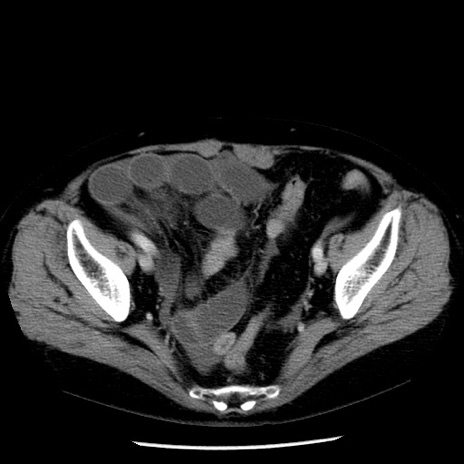

症例13(横断像)

【症例】70歳代女性

【主訴】腹痛、嘔吐

【現病歴】15時間程前(昨晩)より腹痛あり。今朝になっても症状の改善なく、嘔吐あり。腹痛も増悪あり、救急外来受診。

【既往歴】子宮癌全摘術後

【身体所見】意識清明、BP 121/72mmHg、P 74bpm、SpO2 100%(RA)、腹部:平坦・軟、腸雑音ほぼ聴取せず。下腹部・心窩部・臍左上に圧痛あり。反跳痛なし。

【データ】WBC 10600、CRP 0.15